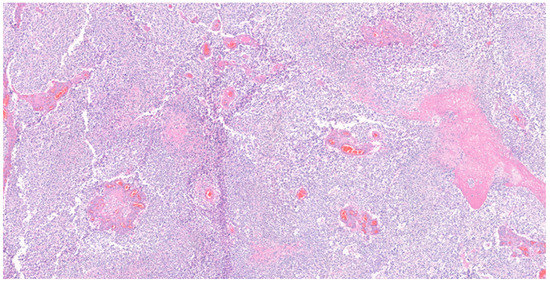

Histopathological analysis of the tumor revealed glioblastoma (WHO grade IV), with increased cellularity, cellular atypia, and frequent mitotic figures. Glomeruloid microvascular proliferation and tumor necrosis were also found Figure 4 and Figure 5. Immunohistochemical (IHC) staining revealed a positive stain of glial fibrillary acidic protein (GFAP), isocitrate dehydrogenase-1 (IDH-1) and alpha thalassemia/intellectual disability X-linked gene (ATRX) Figure 6A–C. A wild-type pattern presentation of p53 protein was also noted Figure 6D. In addition, the other specimen revealed a mixture of abnormally muscularized arteries without continuity and a complete three-layer structure under Masson’s trichrome stain Figure 7. Furthermore, ambiguous vessels exhibiting both artery and vein characteristics that were compatible with AVM under Verhoeff–Van Gieson stain Figure 8.

Figure 4.

Histological examination of the tumor. Necrosis and high cellularity were noted. Numerous blood vessels of varying sizes were also noted within the tumor. Hematoxylin and eosin stain, magnification 50×.